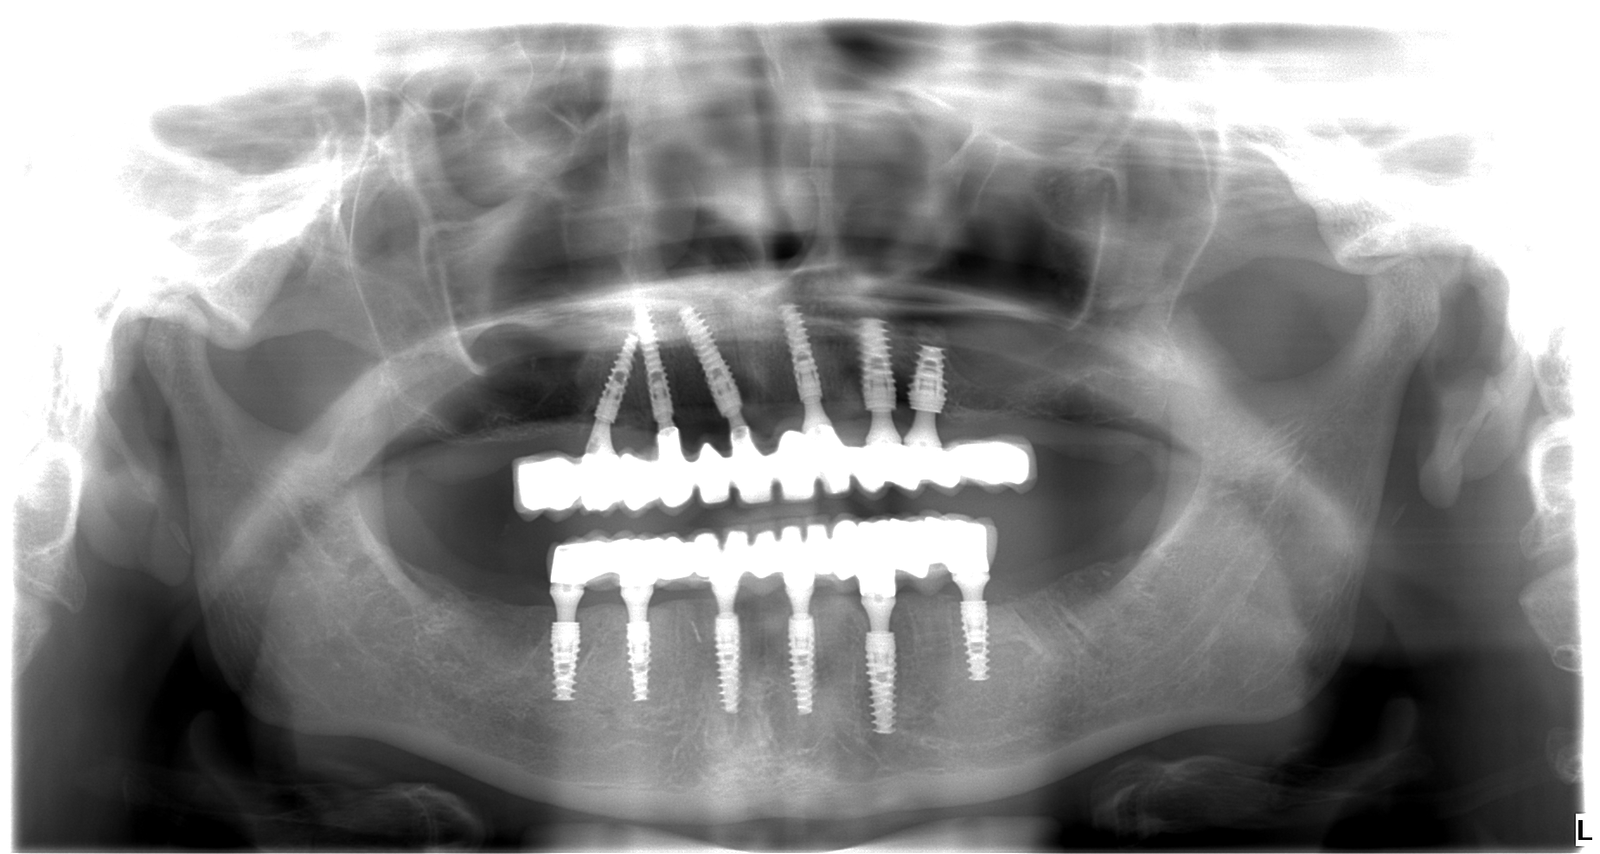

Adriana bola mladá žena, ktorá sa roky trápila s nekompletným a pokazeným chrupom. Hanbila sa smiať, vyhýbala sa foteniu a spoločnosti a spoločenským aktivitám. Rozhodla sa to zmeniť a prišla k nám. Po dôkladnej konzultácii, röntgene a 3D snímke sme jej navrhli plán na mieru: extrakcie nevyhovujúcich zubov, 6 implantátov hore, 6 dole a nový, 12-členný mostík do oboch čeľustí.